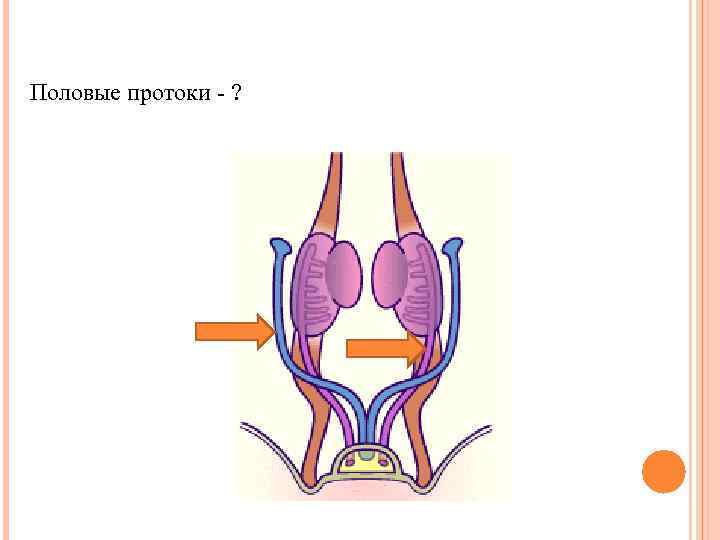

Половые протоки - ?

Половые протоки - ?